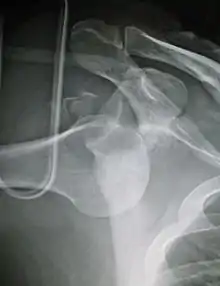

An anterior dislocation of the shoulder

Anterior dislocation of the right shoulder. AP X ray